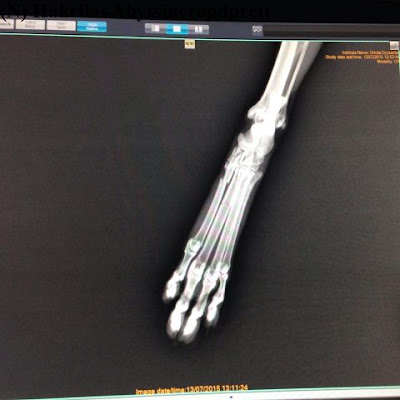

Her er røntgenbilde av Nadina sin labb. Dere ser tydelig det ene beinet som er ute av posisjon, mens beinet ved siden av også var brukket. Det beinet lå fint på plass.

Røntgenbilde av labben til Nadina etter veterinæren hadde fått beinet på plass, og lagt på skinna og polstringen.